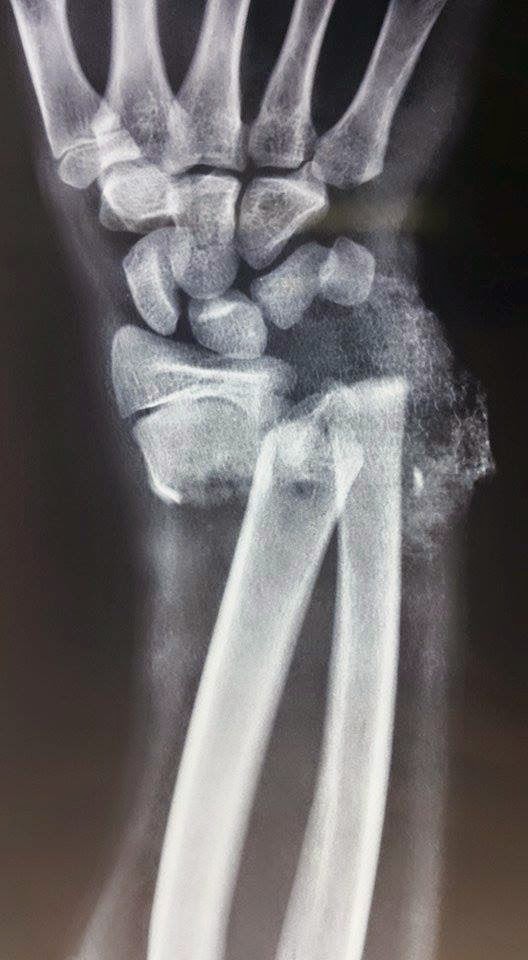

15yrs male presented with closed displaced fracture distal end of radius and ulna with ipsilateral displaced fracture radial head with impending compartment syndrome of forearm .

Fasciotomy of forearm with orif with k wiring distal end of radius and radial head. Planning to do secondary closure after 5days.if i am not wrong its rare presentation

Deepak Patil radial head excise or preserve? lateral elbow xray head looks subluxated

Ajay Pal Singh Kanwar A rare one. radial head fixation requires more imaging..

Naveen Vishwa Probably Essex Lopressatti injury is the cause for compartment syndrome

Is there a rotational mal alignment in distal Radius…??? -